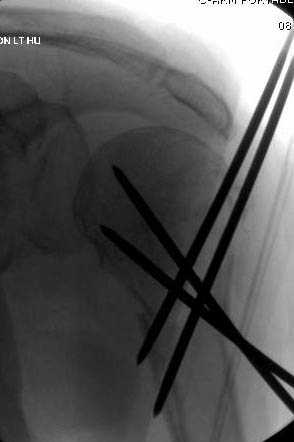

Наличие рентген контроля (ЭОП) помогает во время

репозиции и фиксации, но многие коллеги умудряются без рентгена фиксировать несколькими спицами перкутанно.

Из-за тенденции миграции осторожно со спицами,

особенно у пожилых, слабые кости не выдерживают

нагрузку, были случаи миграции, обнаруженные при первом же амбулаторном приеме, поэтому методика Лазарева напряженными спицами более приемлема, особенно у тех, кто испытывает нехватку фиксирующих конструкций (на сайте

имеется описание техники).

Наш недавний случай перкутанной фиксации "методом

Сиэтла" спицами 2.8 мм с резьбой на конце.